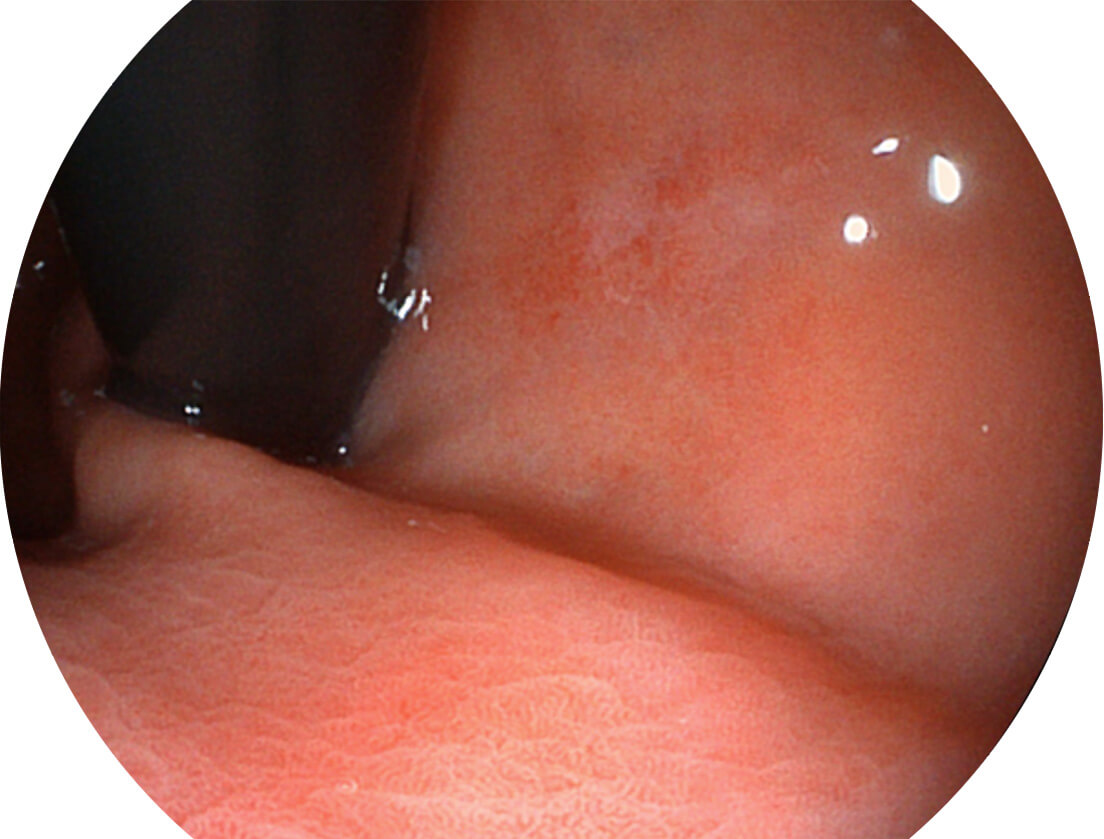

白光图像